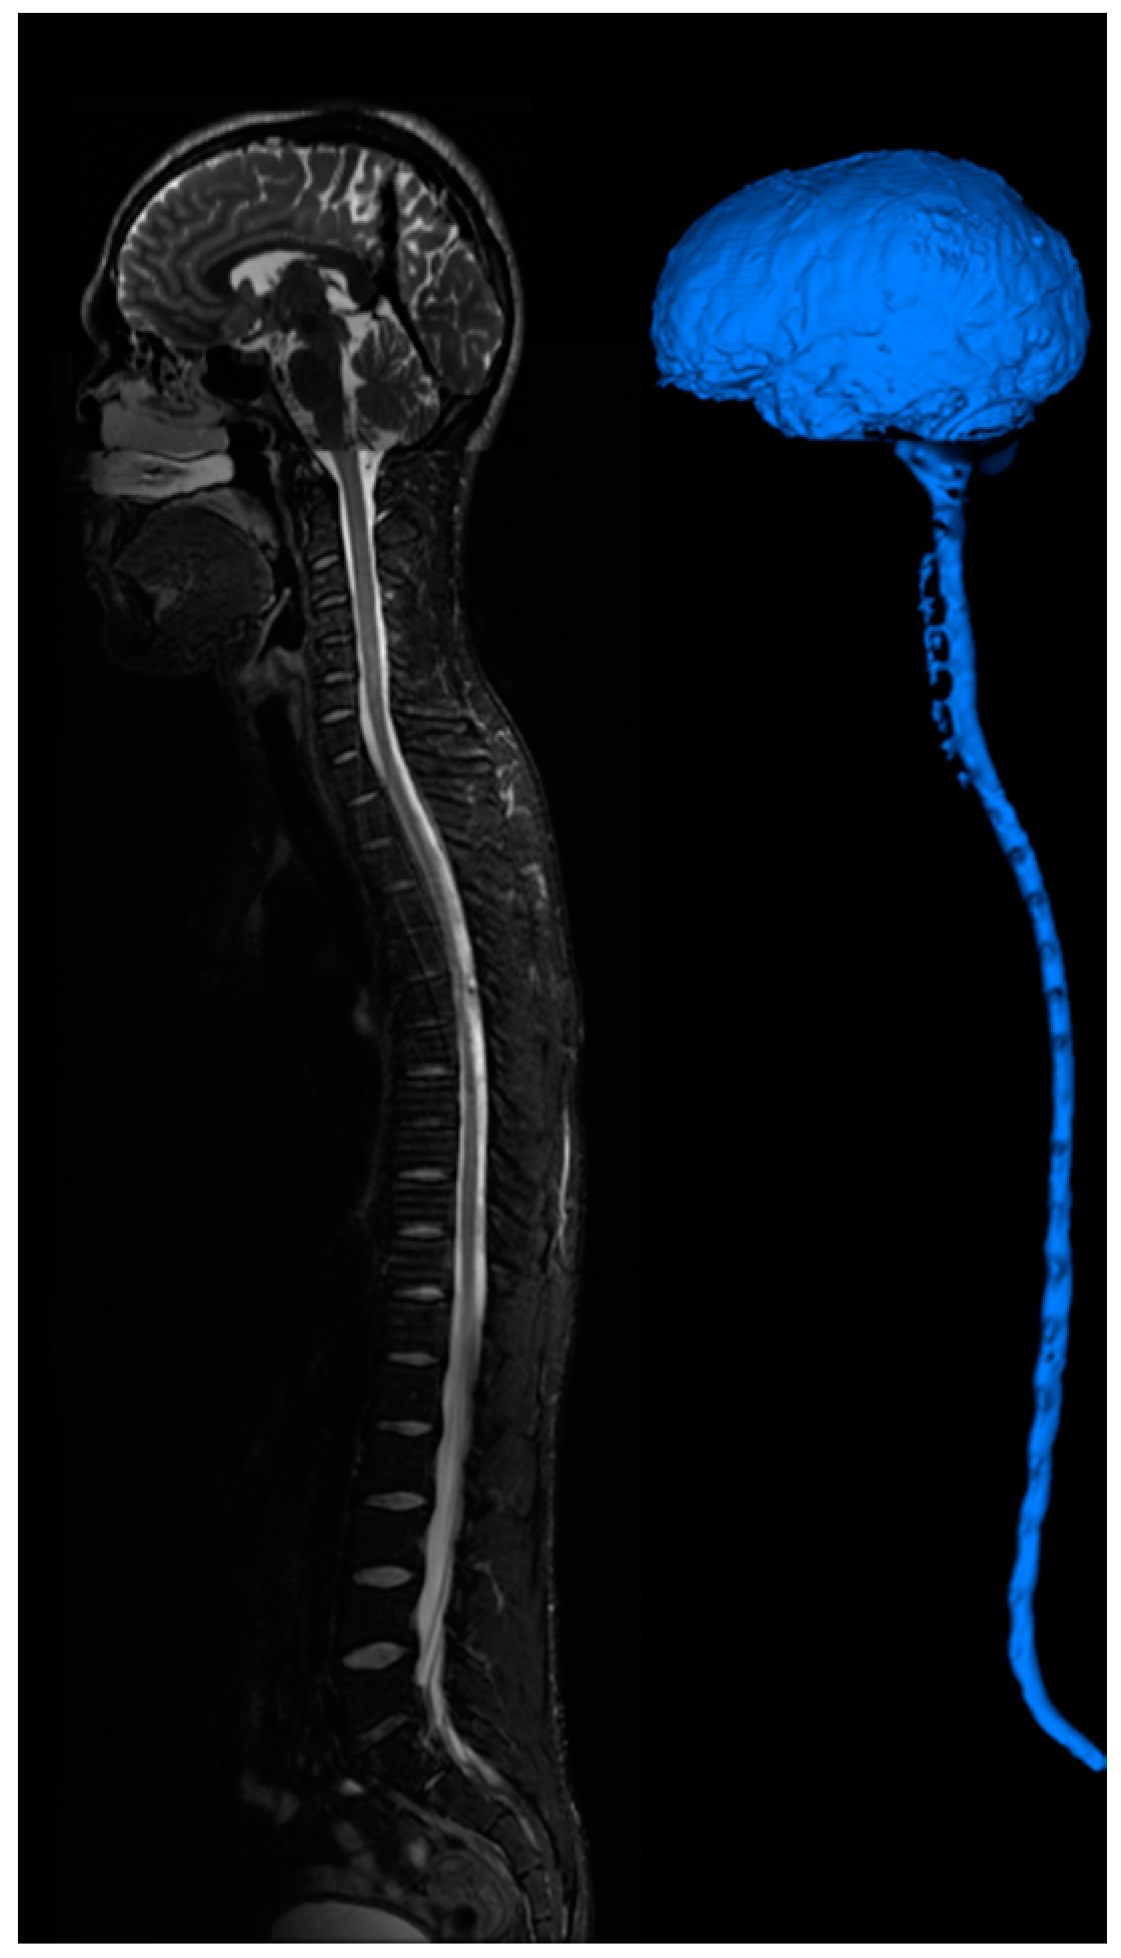

The computational meshes can be used for computational fluid dynamics simulations. Detailed hemodynamic simulation can be achieved by using commercial software solving the 3D Navier-Stokes equation as shown in Figure 6. The meshes are loaded into the software and assigned with boundary conditions. Our 3D simulation demonstrates velocity field, pressure gradient, and dye convection with a pulsatile boundary condition. Figure 6 also shows preliminary hemodynamic simulations for blood flow rate and blood pressure using the cylinder mesh and simplified flow principle equations. The computational time for these simulations are less than one minute. Additionally, we also performed dye convection simulation with time step = 0.1 s for 10 s duration to produce artificial dynamic angiography in Figure 6. The computational time for dye convection is dependent on the step size and in this case it took less than five minutes. The simulation results demonstrate the use of our image processing pipeline for rapid simulation to aid clinical diagnosis. In addition to cerebral hemodynamics, we also acquired images for full body CSF reconstruction along with phase contrast MRI for CSF flow measurements as shown in Figure 7. The CSF model allows us to study full body CSF dynamics [14,17]. Combined with the whole brain model, we can investigate the relationship between cerebral hemodynamics and CSF dynamics.

Figure 7.

CSF imaging for the entire central nervous system. T2 images are acquired for the brain, cervical-thoracic region, thoracic-lumbar region, lumbar-sacral region. Image stitching algorithms were utilized to construct a contiguous image of the entire CSF space. The image is segmented to provide a continuous computational mesh of the entire CSF space.